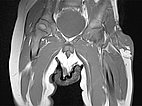

Axial slice of MRI (T2-weighted, fat-saturated) also clearly shows the infiltration of the musculature by the mass. Hemangiomas as vascular tumors can also exhibit such infiltration without necessarily being malignant.

In non-enhanced coronal T1-weighted MRI, the tumor is isointense to the musculature without containing adipose tissue. Thus, it is hardly distinguishable from the musculature in this sequence.

Axial T2-weighted MRI without fat saturation shows the tumor as homogeneous and only slightly hyperintense. It is more hyperintense than muscle, but overall much less hyperintense than the surrounding subcutaneous adipose tissue.

Coronal T1-weighted, fat-saturated MRI after contrast administration. The tumor shows homogeneous, strong enhancement. Inside it, two flow voids as a sign of strong arterial perfusion.